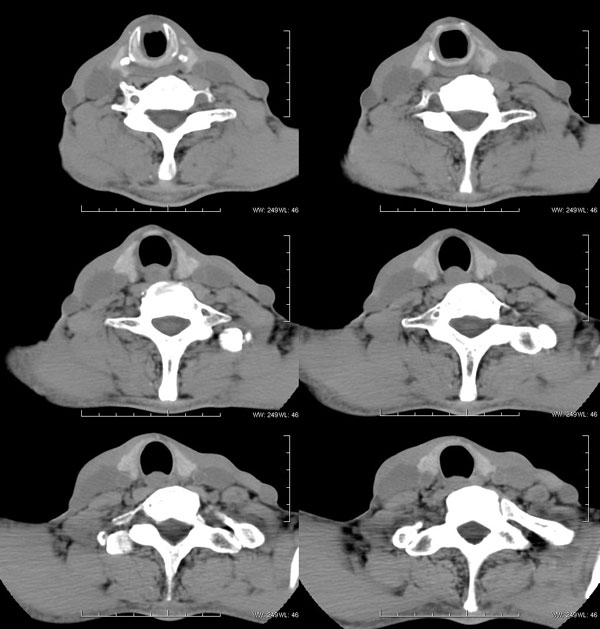

| 男性,57岁。反复声嘶1年,加重半年。 体检:喉粘膜充血,会厌肿胀,上举差,喉室及双声带窥视欠清。              蚂蚁发言:考虑喉癌(声门型)?双侧颈鞘周围淋巴结转移? 徐飞发言:有无呛水?根据病史要考虑球麻痹,脑干应检查 弯三角发言:考虑喉结核,应检查其它部位有无结核 卜一发言:喉腔右侧壁弥漫性软组织增厚,喉腔变窄。支持:喉癌(声门型)!另:双侧颈部多枚淋巴结肿大! 结果: 支纤镜检查:会厌板肿胀,右会厌咽侧壁肿胀,右杓状小结见结节样肿物,喉室肿胀,双声带肿胀、充血,左声带见菜花样肿物,触及易出血,取活检。 病理诊断:高分化鳞状细胞癌。 免疫组化:ck(h)(+++)、pcna(++)、p53(++)、ck(l)(-)。 原贴地址:http://www.radinet.com.cn/forum_view.asp?forum_id=4&view_id=34703 |